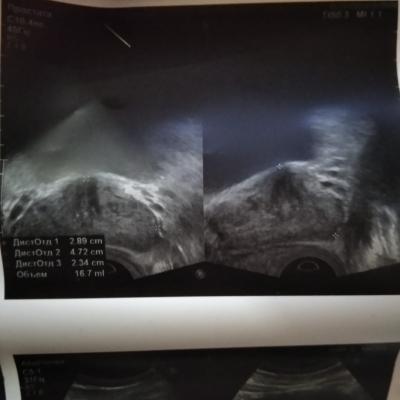

сделали трузи заключение УЗ признаки умеренных диффузорных изменений, размер простаты 2.89,4.72,2.34 обьем 16.7 мл , до этого в поликлинике писали обьем 29.7 см3 и на фото узи белые точки это кальцинаты ?

Здравствуйте! Объём посчитала программа в соответствии с введенными значениями. Белые точки - это маркёры компьютера. Посетите уролога очно. Удачи!